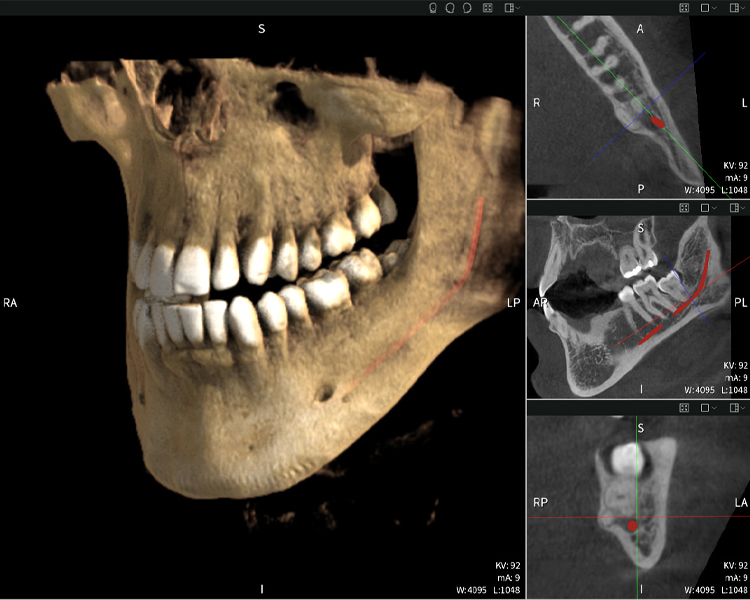

Abbildungen b–d zeigen verschiedene Ansichten einer 3D-Rekonstruktion des Unterkiefers und bieten eine umfassende Übersicht über die Anatomie des Unterkiefers, die Lage der Nerven im Verhältnis zu den Zähnen und ermöglichen die Beurteilung der Zahnsymmetrie und Ausrichtung.

Abbildung d zeigt den bereits vorbehandelte Zahn 48, dessen Krone entfernt wurde und dessen Wurzeln nahe am Nerv belassen wurden, was das hohe Risiko einer Nervenschädigung verdeutlicht.